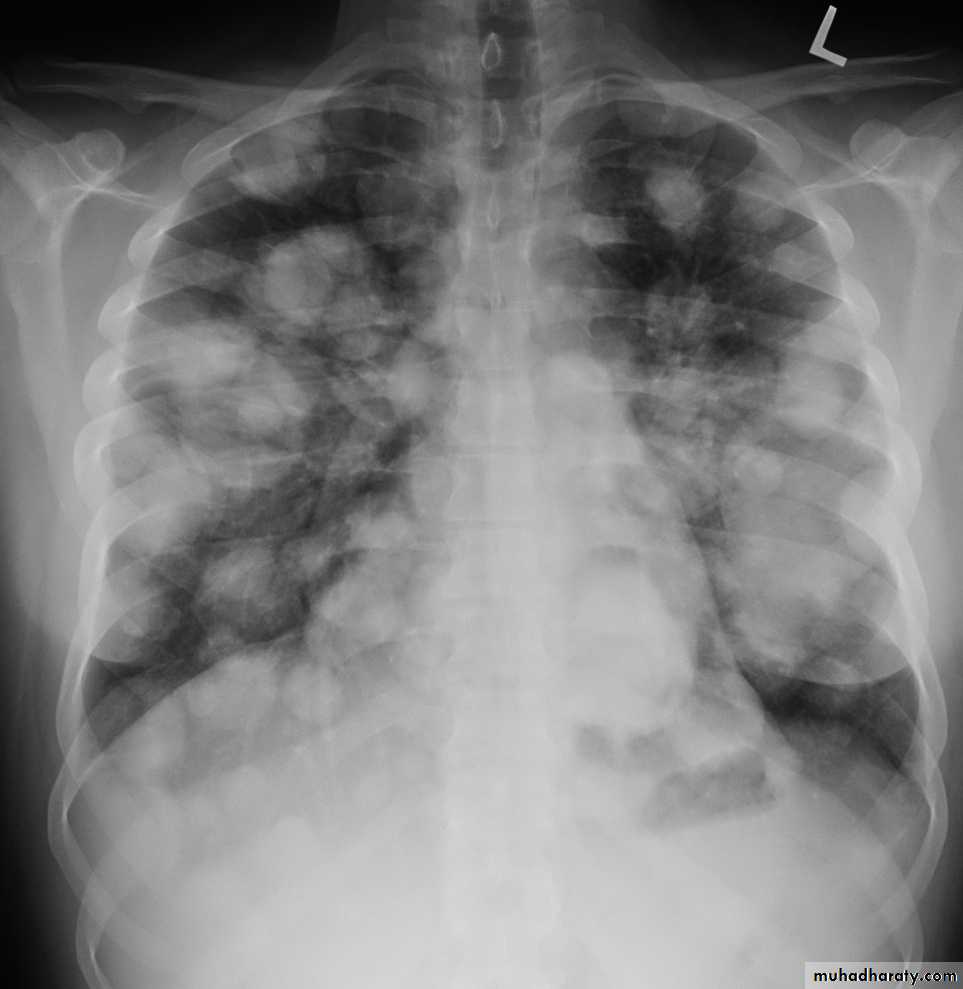

Post primary TB broncho pneumoniacotton wool sign

Post primary TB Bronch pneumonia

60.post primary TB ( cotton wool appearance )

61.post primary TB notice upper apical Broncho pneumonic shadow